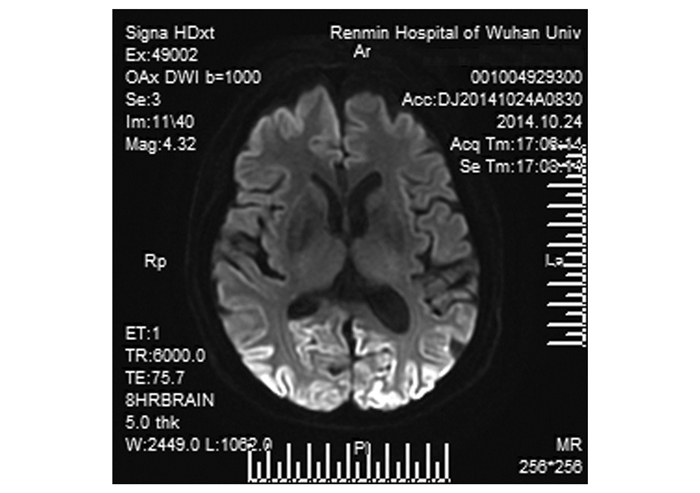

患者入院数天内出现情感淡漠,不能语言交流且运动迟缓,遂请神经内科会诊,检查结果如下:生命体征平稳,颅神经(-),四肢肌张力增高近强直,异常姿势,四肢腱反射低下,深浅感觉正常。追问病史患者半年前有食用生牛肉史。经颅多普勒(TCD)未见异常。MRI-DWI(弥散加权成像,图 2)显示双侧枕顶叶皮层对称性高信号。脑电图提示重度异常脑电图,全头部可见较多慢波、阵发性周期性双向波及三相波(图 3)。脑脊液常规及生化结果正常,寡克隆带阴性。根据上述检查结果并结合患者临床表现,神经内科医师临床诊断为散发型克雅氏病(Creutzfeldt-Jakob disease, CJD)。

图 2 DWI显示双侧枕顶叶皮层可见对称性高信号 |